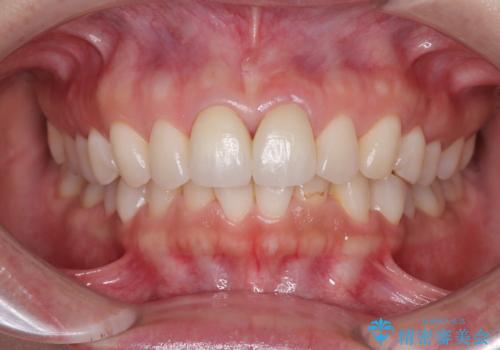

根管治療を行った後に、両歯ともに土台を植立し、オールセラミッククラウンにて補綴治療を行うこととしました。

黄ばみや厚みが改善され、まるで本物の歯のように調和した口元となりました。